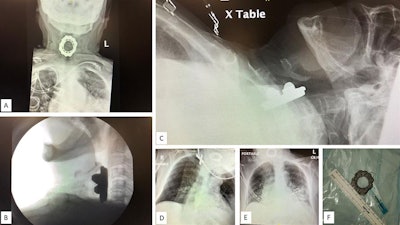

Three days after she was admitted to the hospital, a new medical team took over and noticed the woman had noisy breathing, which occurs with obstructed air flow. The team reexamined the previously obtained chest x-ray and brain and chest CT scans. The images revealed a large foreign body in the woman's hypopharynx-upper esophagus. The object was not described in the report initially read by junior radiology residents.

The patient failed a swallow study, and images were acquired of her neck soft tissue and anterior-posterior cervical spine, which revealed a 5.4 x 2.3 x 4.3-cm foreign body lodged in her hypopharynx anterior to the C3-C6 vertebrae, the authors wrote.

The woman was placed under general anesthesia to avoid erratic movements that could result in puncturing her esophagus. An otorhinolaryngologist surgeon used direct laryngoscopy and angled forceps for the extraction. Rapid sequence induction without application of cricoid pressure was used due to the position of the object, which was a spinning top toy, they wrote.